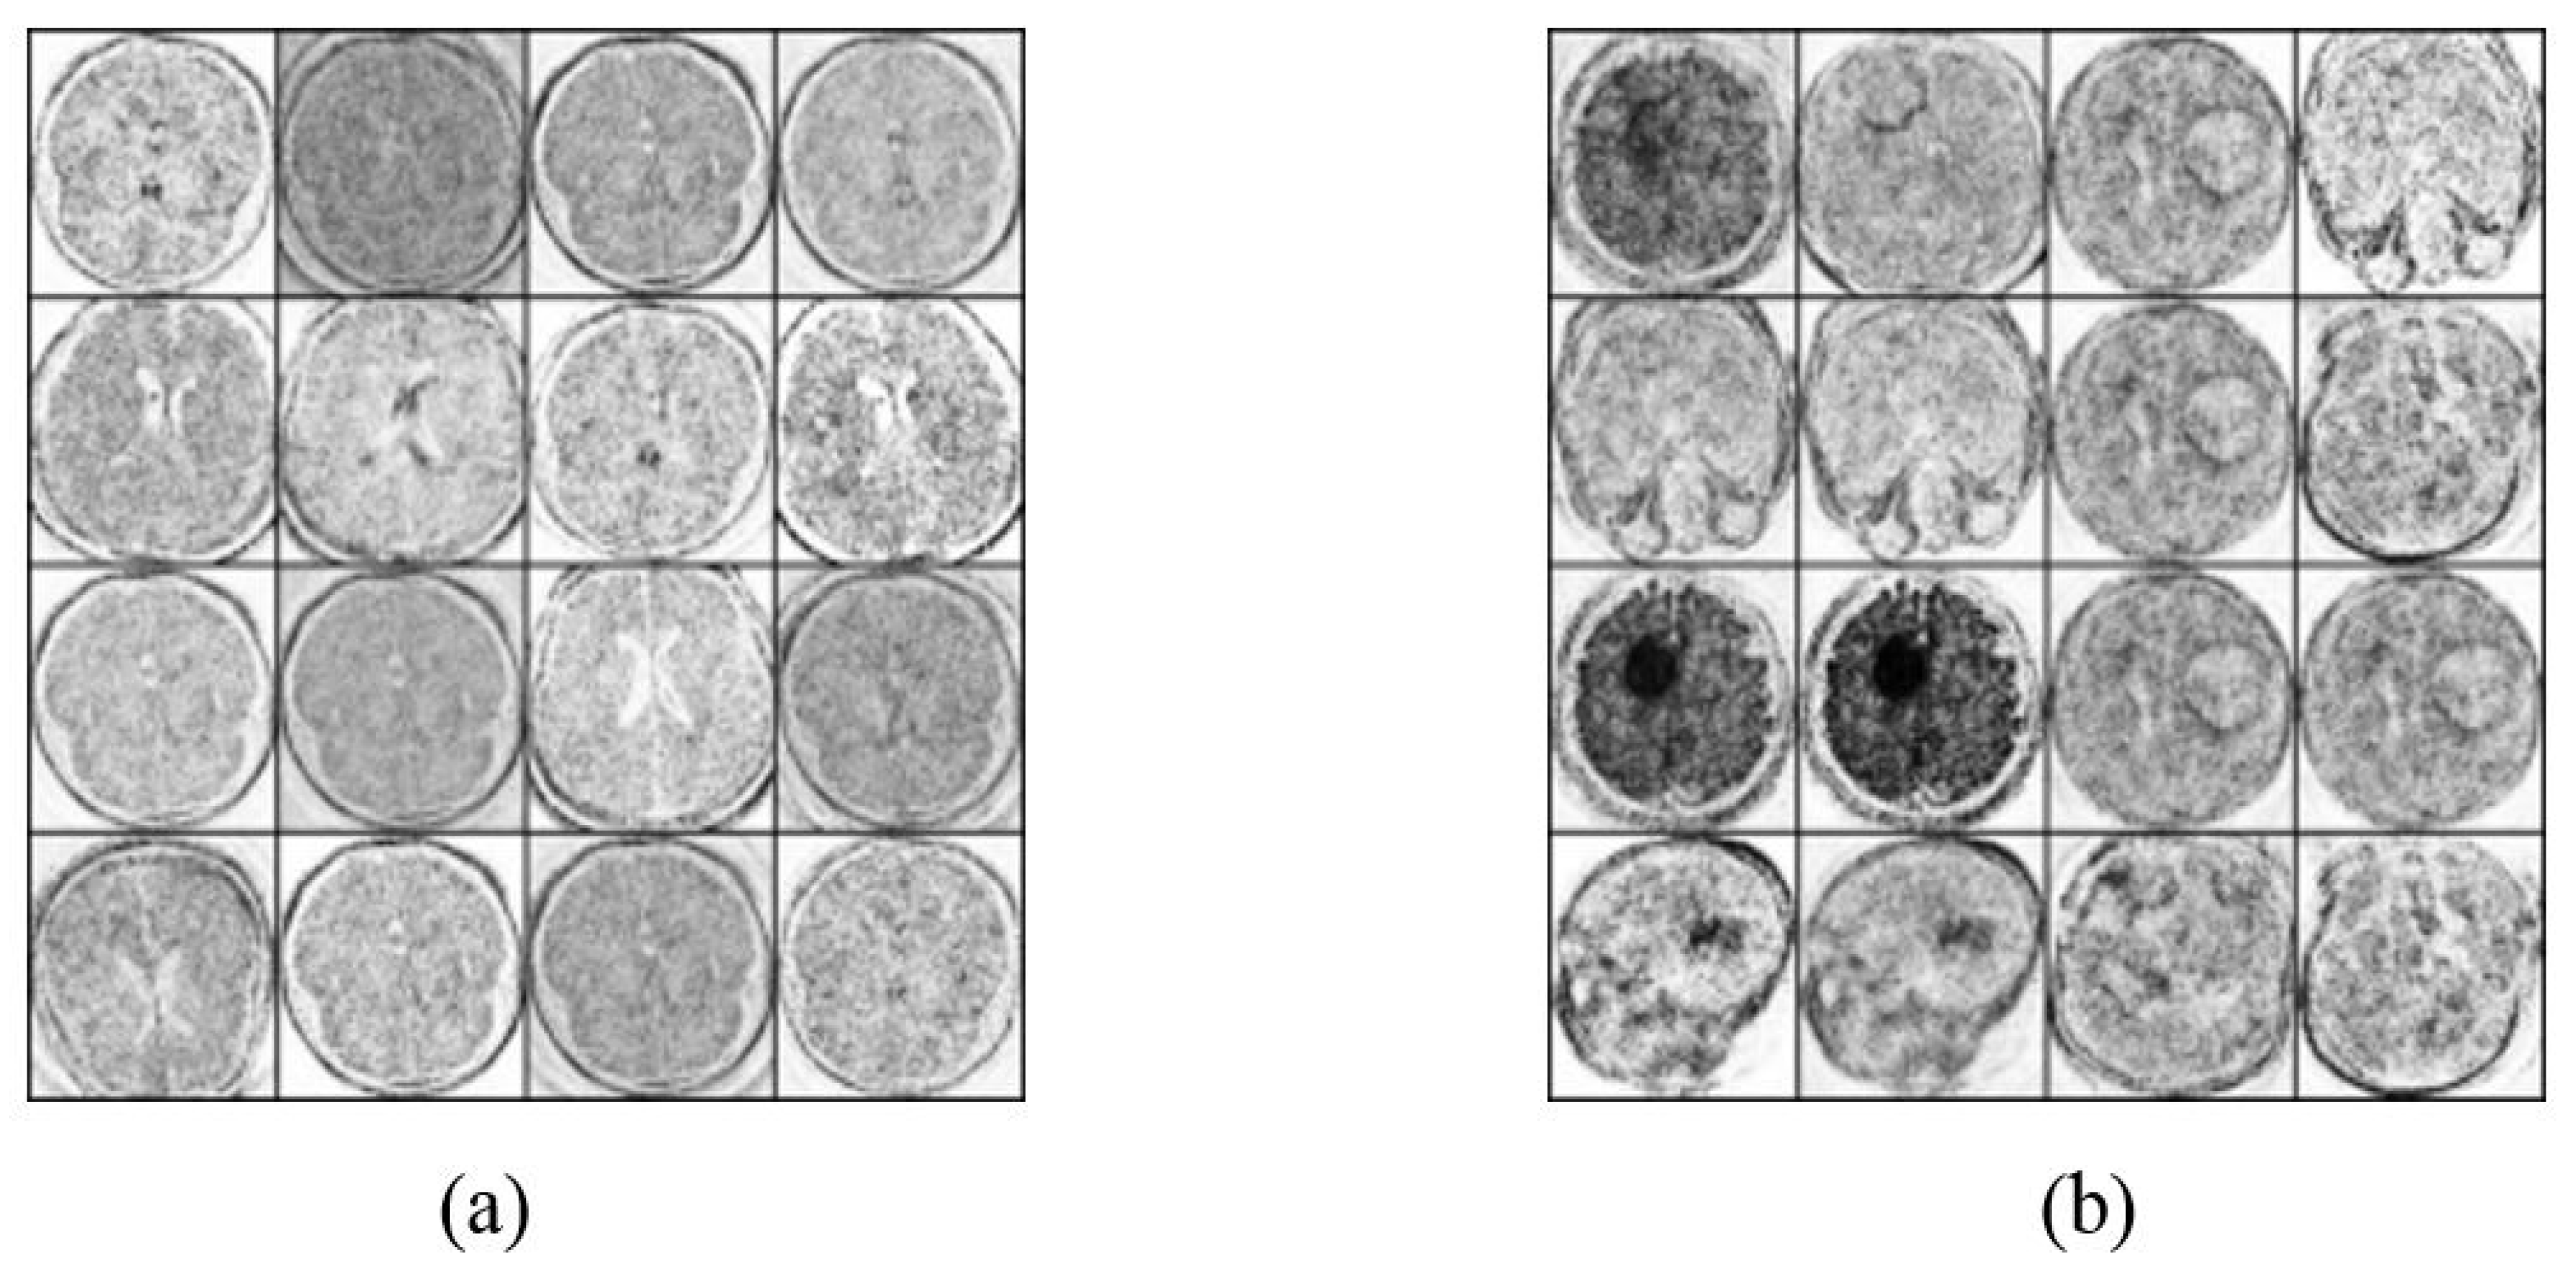

4.2. Image Augmentation Using Vanilla GAN and DCGAN